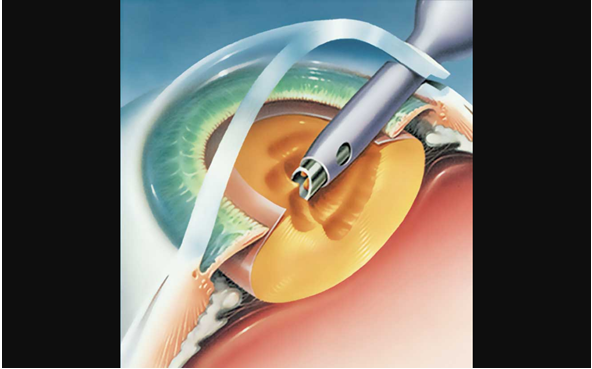

Lentes Intraoculares Suturada a Sulcus Visioncore Cl nica outlet, Reposicionamiento intercambio de lentes intraoculares outlet, Qu son los lentes intraoculares Como Cuidar Los Ojos outlet, Implante de una Lente Intraocular Multifocal M PLUS outlet, Visian ICL lentes intraoculares f quicas outlet, Cirug a Presbicia lentes intraoculares Hospital Universitari outlet, Tipos de lente intraocular en la cirug a de catarata Cl nica outlet, Lente intraocular f quico cirug a que permite dejar de usar outlet, Lentes ICL o Lentes Intraoculares Ventajas e Indicaciones outlet, LENTES INTRAOCULARES Centro de Ojos Buenos Aires outlet, Implante de lentes intraoculares todo lo que debes saber outlet, Todos sobre la operaci n de cataratas con lente intraocular outlet, Cirug a refractiva con lentes intraoculares ICL rea Oftalmol gica outlet, Lentes intraoculares efectos secundarios y complicaciones Blog outlet, Lentes intraoculares para miop a outlet, Implantaci n de lente intraocular de c mara anterior outlet, Cirug a refractiva con lentes intraoculares Miranza outlet, Lentes intraoculares ICL en qu casos est n indicadas Blog D outlet, Cirug a refractiva con lentes pseudof quicas Instituto outlet, Centro Peruano del Pterigion Cirug a de CATARATA Implante de outlet, Cirug a refractiva con lentes intraoculares XR Oftalmolog a outlet, El Lente Intraocular se utiliza toda la vida Beneficios y Costo outlet, Cirug a refractiva con Lentes Intraoculares ICL en Madrid outlet, Lentes Intraoculares F quicas introducci n y complicaciones outlet, Cirug a refractiva con lentes intraoculares en Turqu a Tour for Cure outlet, Qu problemas pueden causar las lentes intraoculares outlet, Qu es una lente intraocular t rica outlet, CIRUG A CATARATA FACOEMULSIFICACION LENTE INTRAOCULAR outlet, Sorpresa refractiva por error en el c lculo de lente intraocular outlet, Precio de lentes intraoculares Operaci n de Ojos outlet, Lentes intraoculares LIO para cataratas premium asf ricas y outlet, Lente intraocular en qu consiste la operaci n y cu ndo se outlet, Lentes intraoculares en la cirug a de catarata Vista Instituto outlet, Implante de Lente Intraocular Dr Gabriel Oliveros outlet, Video Lentes intraoculares para la operaci n de miop a una outlet, Lentes intraoculares ajustables El futuro est aqu outlet, La cirug a de implante de lentes intraoculares para la presbicia outlet, Tras las lentes intraoculares m s de un 40 sufre cataratas a los outlet, Oftalmocentro San Javier outlet, Cirug a L ser Refractiva Lente Intraocular Visian ICL outlet, Sorpresa refractiva por error en el c lculo de lente intraocular outlet, Lente intraocular Cl nica oftalmol gica VISTA S nchez Tranc n outlet, Reemplazo de lente y la cirug a de las cataratas American outlet, Conoce todo sobre un lente intraocular Top Doctors outlet, Cirug a de Catarata Centro Oftalmol gico Doctores Adrogu outlet, El Hospital Mancha Centro empieza a implantar lentes intraoculares outlet, ACTUALIZACION EN LENTES INTRAOCULARES . Dra. Gloria Carretero Leon outlet, Lentes intraoculares f quicas outlet, EN QU CONSISTE LA CIRUG A DE CATARATA Instituto Oftalmol gico outlet, CAMPA A DE LENTES INTRAOCULARES ICL Vithas Eurocanarias outlet.

Cirugia de lentes intraoculares outlet